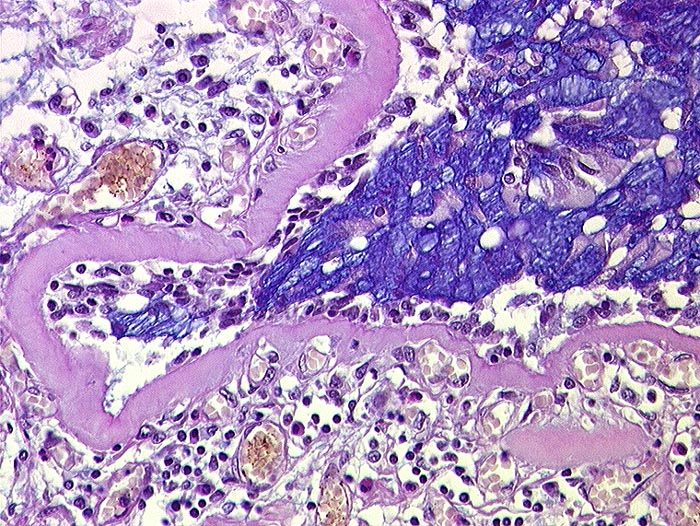

AP/ Asthma bronchiale

Asthma bronchiale

Bronchus

Morphologie

Pathologischer Befund